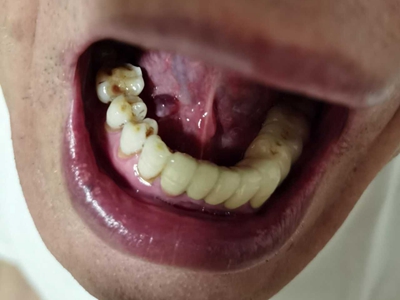

舌下腺囊肿舌头下面右侧有一个紫色包块图

舌下腺囊肿出现在口底舌系带一侧,表现为紫蓝色的隆起性包块,形态大致呈球形,界限清楚,质地柔软,囊肿增大后因破裂流出黏液。